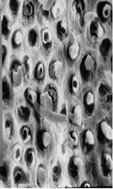

采用牙科用磷酸酸蝕劑對牙本質(zhì)表面進(jìn)行酸蝕處理,能有效去除玷污層,使管周牙本質(zhì)脫礦溶解,牙本質(zhì)小管開口處管徑增大,膠原纖維網(wǎng)暴露,見圖2。這種結(jié)構(gòu)能夠使粘接劑與管間牙本質(zhì)形成微機(jī)械粘接,且有利于粘接劑滲入牙本質(zhì)小管內(nèi)形成樹脂突,從而增大粘接強(qiáng)度。

圖2 牙本質(zhì)表面酸蝕前后形態(tài)掃描電鏡圖示例

如圖2所示,(左)酸蝕前,牙本質(zhì)有玷污層覆蓋;(右)酸蝕后,表面較粗糙,玷污層已被去除,部分牙本質(zhì)小管開放,管間牙本質(zhì)膠原纖維網(wǎng)充分暴露。